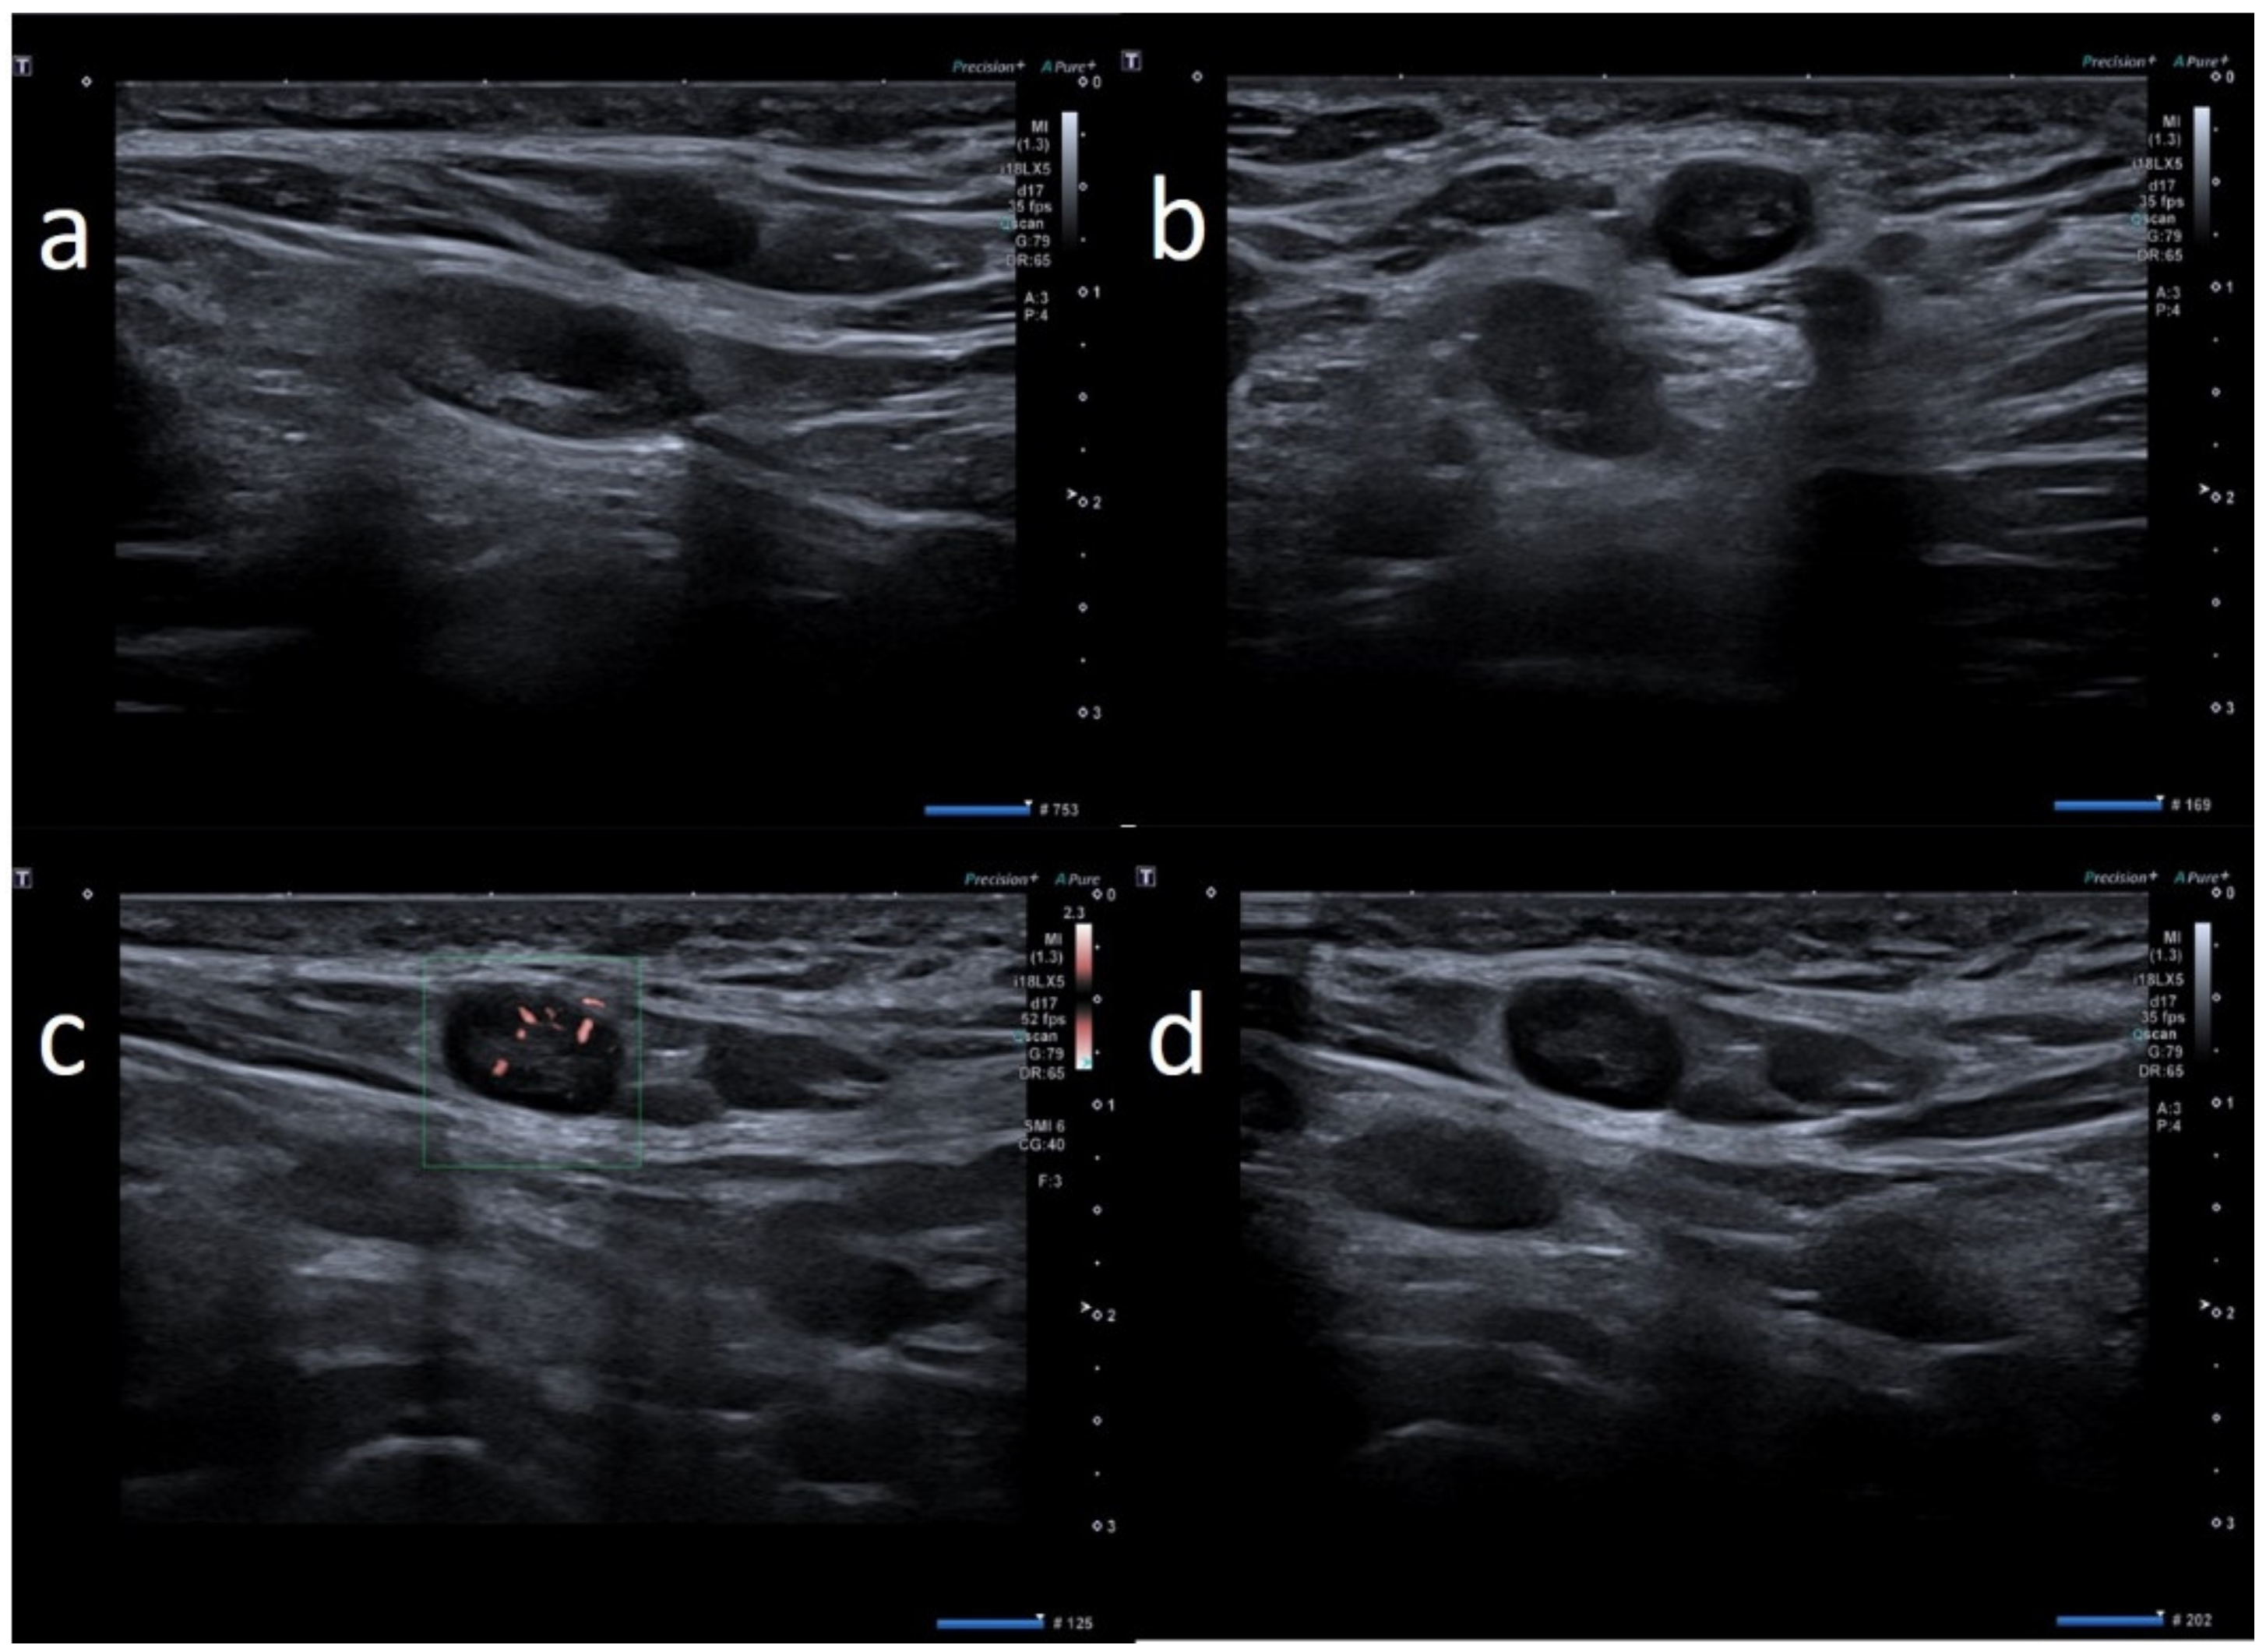

| W | 25 | Pfizer | Axillary ipsilateral to vaccine injection | Three days after first dose of vaccine, axillary swelling and pain present. Also hypomobility ipsilateral arm | None | 6 | Variable: from 0.7 cm to 2.8 cm | Ovular | Prev. no hilum evidence | Prevalent hard pattern | Central and peripheral vascular signals | Normalized to 60 days |

| W | 49 | Pfizer | Axillary ipsilateral to vaccine injection | Occasionally, 6 days after first dose, during breast sonography for oncological surveillance | Breast cancer 3 years ago | 4 | Variable: from 1.0 to 2.0 cm | Ovular | Asimmetric cortical thickening and poor evidence hilum | Stiffness similar to surrounding tissue | Central and peripheral vascular signals | Unnecessary other follow-up |

| W | 54 | Pfizer | Axillary ipsilateral to vaccine injection | Occasionally, 14 days after second dose, during breast sonography for surveillance | None | 3 | Variable: from 1.0 to 2.0 cm | Ovular | Simmetric cortical thickening with normal hilum | Stiffness similar to surrounding tissue | Normal | Unnecessary other follow-up |

| W | 52 | Pfizer | Axillary ipsilateral to vaccine injection | Occasionally during breast sonography for oncological surveillance | None | 3 | Variable: from 1.0 to 2.5 cm. | Ovular | Simmetric cortical thickening with normal hilum | Stiffness similar to surrounding tissue | Normal | Unnecessary other follow-up |

| W | 53 | Pfizer | Axillary ipsilateral to vaccine injection | Occasionally, 16 days after first dose, during breast sonography for oncological surveillance | Breast cancer 2 years ago | 3 | Variable: from 1.0 to 2.0 cm | Ovular | Asimmetric cortical thickening with hilum evidence | Stiffness similar to surrounding tissue | Normal | Unnecessary other follow-up |

| M | 62 | Pfizer | Axillary ipsilateral to vaccine injection | Occasionally, 2 weeks after first dose, during chest ct to monitor small polmonary nodules | None | 3 | Variable: from 1.5 to 2.0 cm. | Ovular | Simmetric cortical thickening with normal hilum | Stiffness similar to surrounding tissue | Normal | Unnecessary other follow-up |

| W | 37 | Pfizer | Axillary ipsilateral to vaccine injection | Three days after first dose vaccine, axillary swelling present | Melanoma 5 years ago | 5 | Variable: from 1.5 to 2.0 cm. | Ovular | Assimetric cortical thickening with hilum evidence | Prevalent hard pattern | Central and peripheral vascular signals | Normalized to 45 days |